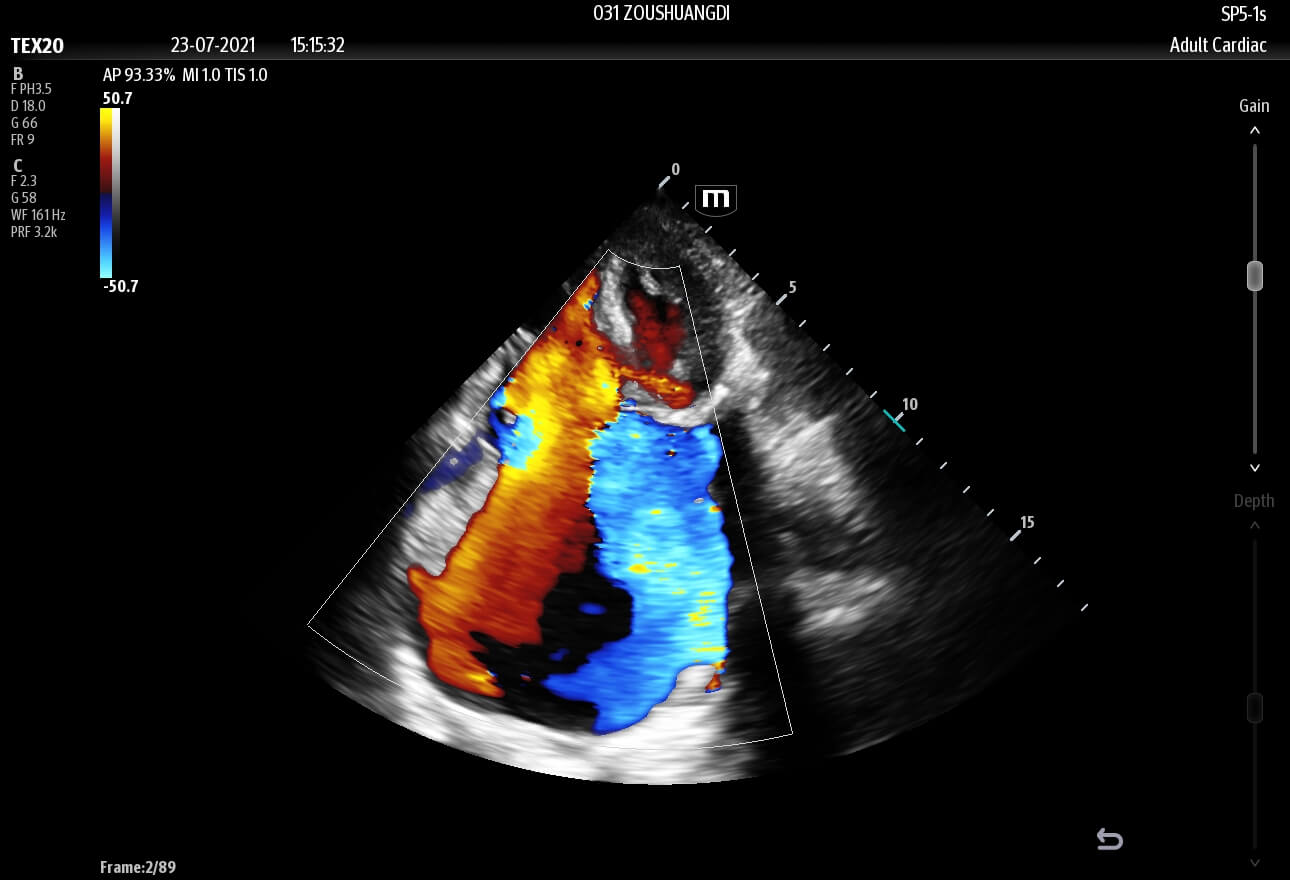

Inspired by the increasing clinical demands of today’s challenging healthcare environment, the touch-based TE X Ultrasound System adopts advanced technologies and integrates them into an innovative, accessible, and patient-centered solution.

The technology-rich TE X Ultrasound System gives clinicians access to market-leading artificial intelligence (AI)-powered Smart Tools, an ergonomically designed system, and proprietary software-based beamformer Zone Sonography Technology+ (ZST+). By incorporating these elements, the TE X Ultrasound System provides access to advanced diagnostic data, the ability to adapt to the various clinical scenarios at point of care, and best-in-class imaging to help them provide a higher standard of care.